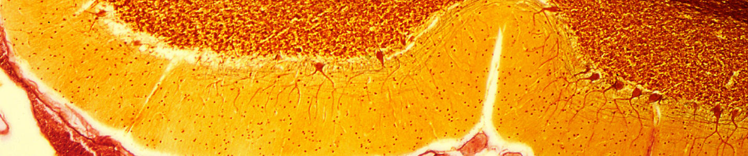

CELLULES DE PURKINJE DANS LE CERVELET

Changements dans le cerveau vieillissant

Les changements physiques du cerveau qui sont associés au vieillissement comprennent :

- Atrophie (rétrécissement) des tissus de certaines régions

- Augmentation du volume ventriculaire

- Perte des neurones et des synapses et diminution de la formation de nouveaux neurones

- Accumulation anormale de protéines